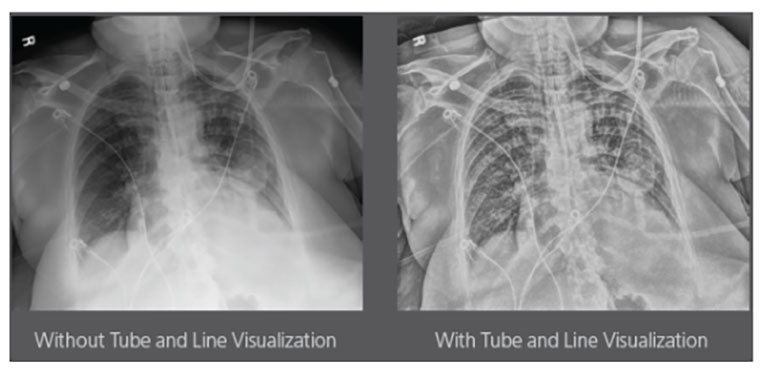

Upgrading your imaging system to a solution designed for outstanding image quality is no longer out of reach — it's now easier, more affordable, and more effective than ever before.

Our Carestream Focus HD 35/43 Retrofit Detectors, powered by Image Suite Software, are an ideal solution to step up to full digital X-ray for customers who simply cannot compromise on image quality. It seamlessly integrates into existing setups, bringing the power of full digital X-ray with minimal disruption and maximum clarity, along with the following benefits: